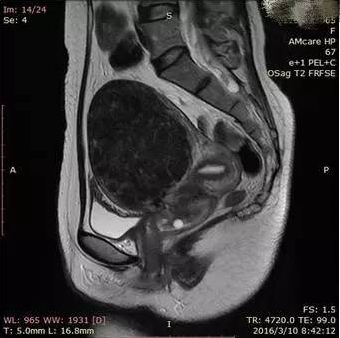

图2. 后倾的子宫前方有肠管存在,影响超声波的穿透

(1)在治疗的靶区之前是否存在着肠管等影响超声波通透的肠管,超声波对于空腔脏器是容易产生反射和折射的,所以若是在子宫前方存在着肠管等,超声波就不能穿透。当然有的时候通过直肠内打胶或者推挤膀胱的方式也可以将肠管排空,后倾后屈的子宫往往不容易成功。图1中治疗的靶区子宫紧贴着腹壁,超声波能量容易通过,就是适合于磁波治疗的情况。图2中子宫后倾,前方有不少肠管组织在,肠管会影响超声波的穿透,就不是特别适合做磁波治疗。